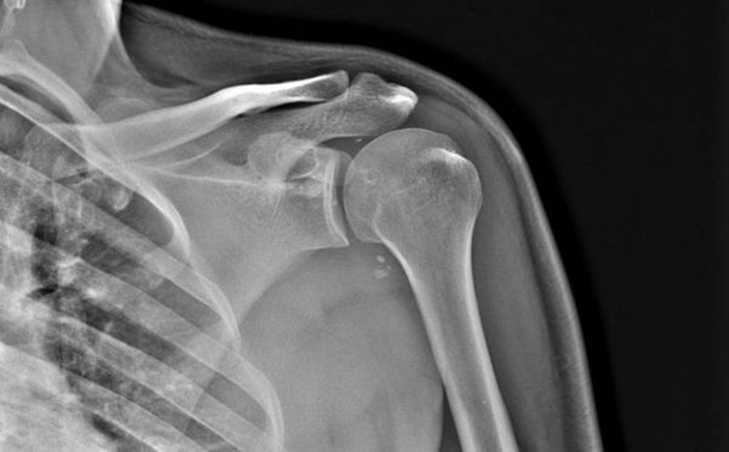

РОЗПІЗНАЙТЕ НА РЕНТГЕНОГРАМІ СУГЛОБ, ЩО МАЄ МІЛКУ СУГЛОБОВУ ЗАПАДИНУ І СКРІПЛЕНИЙ ПЕРЕВАЖНО М'ЯЗАМИ, ТОМУ ТУТ ВІДНОСНО ЧАСТО БУВАЮТЬ ВИВИХИ.

варіанти відповідей

НА ЯКИЙ СУГЛОБ ВКАЗУЄ СТРІЛКА НА РЕНТГЕНОГРАМІ? КІСТКИ ЯКОГО ВІДДІЛУ СКЕЛЕТУ ВІН З'ЄДНУЄ?

ГРУДНИННО-КЛЮЧИЧНИЙ С.

ПЛЕЧОВИЙ С.

НАДПЛЕЧОВО-КЛЮЧИЧНИЙ С.

АКРОМІАЛЬНО-КЛЮЧИЧНИЙ С.

КІСТКИ ВЕРХНЬОЇ КІНЦІВКИ

КІСТКИ ТУЛУБА І ВЕРХНЬОЇ КІНЦІВКИ